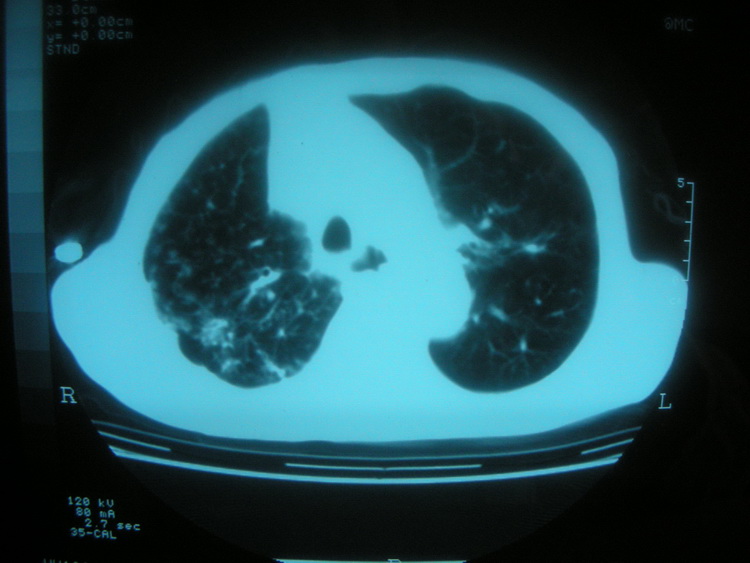

以下是引用卜一在2008-2-16 6:10:00的发言:[br]右肾增大,实质内明显见占位性病灶,并突出体外,密度不均匀。另双肺上叶见散在的斑片 索条及点状结节样致密影,右下肺门区不规则团块,右侧胸腔积液并形成局限性气胸。考虑:1 右肾癌。2 右肺门淋巴结转移及肺内 胸膜转移。3 右上肺陈旧结核。